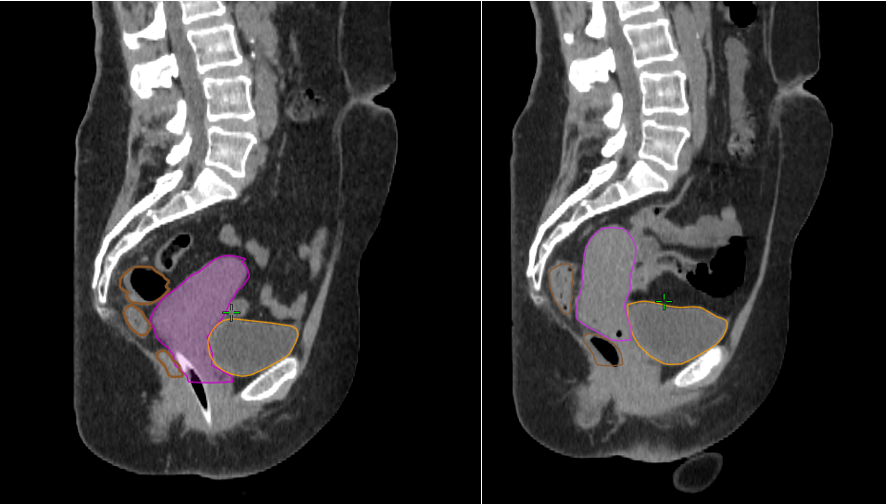

Contourage

Etape durant laquelle votre oncologue-radiothérapeute détermine les zones à traiter et les organes sains à protéger. Il va s’aider des différents examens réalisés. Des outils informatique d’aide au contourage peuvent être utilisés notamment via des outils basés sur l’IA (Intelligence Artificielle).

Radiothérapie Adaptative

La radiothérapie adaptative consiste à adapter le traitement de radiothérapie planifié initialement, en prenant en compte les changements quotidiens dans l’anatomie du patient (déformation ou réduction du volume tumoral, amaigrissement du patient).